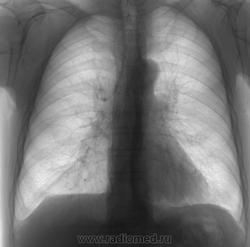

здравствуйте Виктор Григорьевич! простите меня за тупоглазость, но на боковухе я ее потерял

Да я и сам ее на боковухе потерял

....будем искать

....КТ назначил....

А как же скопия?

Виктор Владимирович...на моем то 27-летнем РУМе....ну найду я ее, к примеру...что это мне добавит...ровным счетом ничего....уж больно небольшая и нежная эта тень....

Виктор Григорьевич никак не мог себе представить, что "зубры" работают на "динозаврах" ))... на мой взгляд скопия, вероятно, помогла локализовать образование, чо возможно позволило бы выполнить линейную томограмму, что помогло бы в верификации процесса. Но КТ конечно лучше! (жаль что дольше)